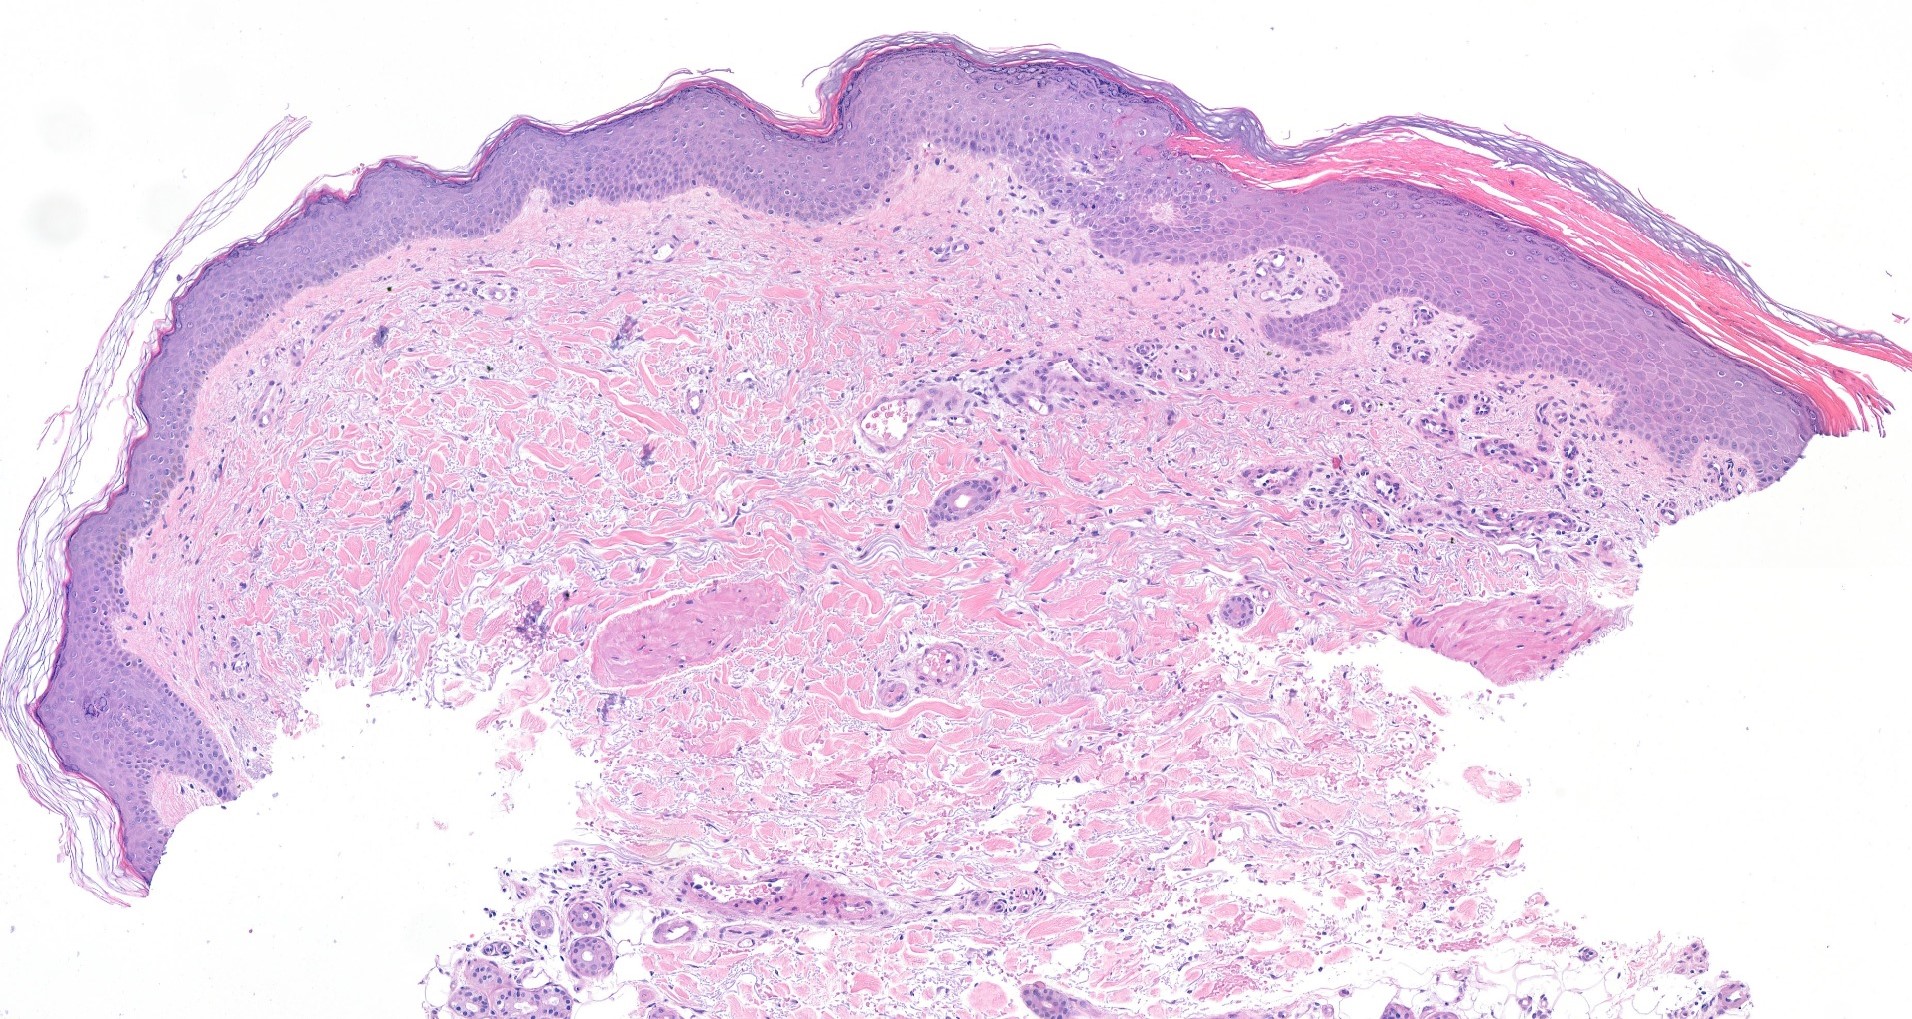

De diagnose porokeratose wordt door een ervaren behandelaar doorgaans gesteld op basis van het uiterlijk van de huid. De kenmerkende schilferende rand en de typische locatie zijn vaak al richtinggevend. Bij twijfel wordt een huidbiopsie verricht: een klein stukje huid wordt weggenomen en onder de microscoop onderzocht. De cornoid lamella is dan duidelijk herkenbaar. Bij porokeratose ptychotropica is een biopt vrijwel altijd noodzakelijk voor een betrouwbare diagnose, omdat het uiterlijk van de afwijkingen sterk kan lijken op andere aandoeningen.